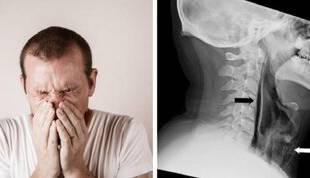

سوراخ شدن گلو بر اثر نگه‌ داشتن عطسه

آیا پیش آمده در جلسه‌ای رسمی باشید و برای اینکه ادب را رعایت کرده باشید، عطسه‌تان را نگهدارید. این کار را مردی در بریتانیا انجام داد و در نهایت مجبور شد، با سوراخی در گلو خود را به بیمارستان برساند.